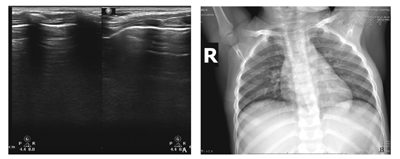

A.肺部超声可见双肺内多处胸膜线增厚,可见多条融合B线及多个大小不等的斑片状弱回声区,后下肺内融合B线,呈瀑布样。弱回声区,形态不规则,可见支气管充气征。B.X线胸片可见双肺纹影及肺门影稍紊乱、模糊,肺野内中带分布斑点、条絮状模糊影。

A.治疗6 d后肺部超声可见双下肺局部胸膜线模糊,A-线出现,右下肺散在B-线,其余区域未见异常;B.治疗6 d后X线胸片可见双肺纹理稍粗多、模糊,肺野内见少许条絮状,肺炎炎症大部分吸收。